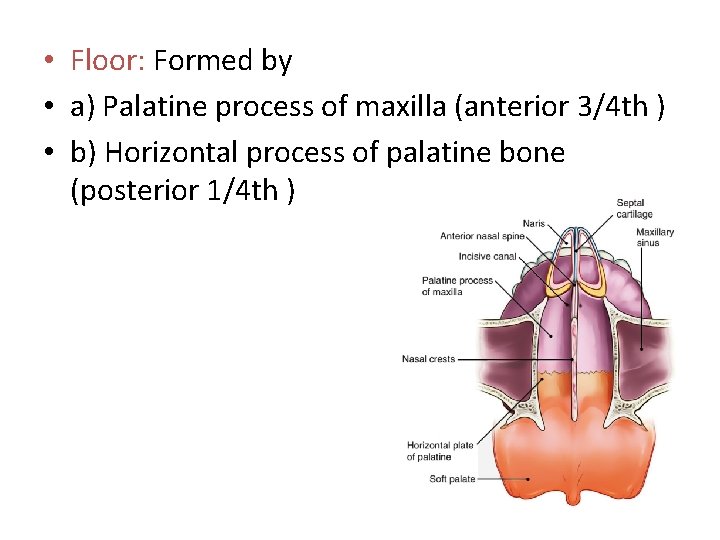

• Floor: Formed by • a) Palatine process of maxilla (anterior 3/4 th ) • b) Horizontal process of palatine bone (posterior 1/4 th )